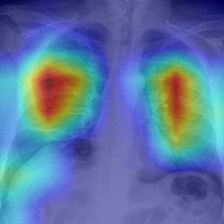

Recent epidemiological data report that worldwide more than 53 million people have been infected by SARS-CoV-2, resulting in 1.3 million deaths. The disease has been spreading very rapidly and few months after the identification of the first infected, shortage of hospital resources quickly became a problem. In this work we investigate whether chest X-ray (CXR) can be used as a possible tool for the early identification of patients at risk of severe outcome, like intensive care or death. CXR is a radiological technique that compared to computed tomography (CT) it is simpler, faster, more widespread and it induces lower radiation dose. We present a dataset including data collected from 820 patients by six Italian hospitals in spring 2020 during the first COVID-19 emergency. The dataset includes CXR images, several clinical attributes and clinical outcomes. We investigate the potential of artificial intelligence to predict the prognosis of such patients, distinguishing between severe and mild cases, thus offering a baseline reference for other researchers and practitioners. To this goal, we present three approaches that use features extracted from CXR images, either handcrafted or automatically by convolutional neuronal networks, which are then integrated with the clinical data. Exhaustive evaluation shows promising performance both in 10-fold and leave-one-centre-out cross-validation, implying that clinical data and images have the potential to provide useful information for the management of patients and hospital resources.